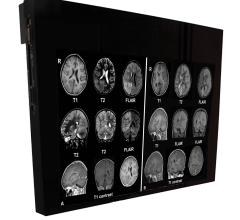

Recent guidelines seeking to reduce the use of neuroimaging tests for patients with headaches run the risk of missing or delaying the diagnosis of brain tumors, according to an article in Neurosurgery.

Double Black Imaging released a new MRI safe display at RSNA 2014.